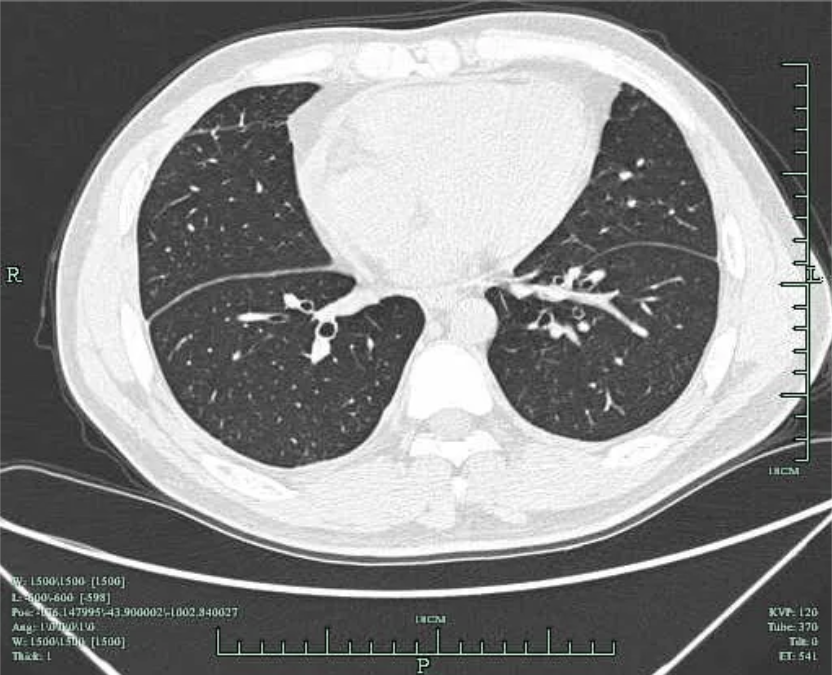

住院过程中,追问患者为面馆老板,否认食用生鱼、醉虾、醉蟹等,回忆起患病前1周曾有一次修理摩托车过程中遭低压(220V)电击,当时有左侧胸痛,全身麻刺感,随后隐约觉得左侧胸痛,刺痛或隐痛,未重视;此次入院后经抗感染、胸水引流、心包积液引流等处理,复查胸水明显减少,心包积液减少,约半年随访复查肺部CT 两肺未见实质性病灶(图5),未见胸腔积液,未见心包积液,故此次胸腔积液及心包积液考虑低压电击后心肌损伤,胸部钝挫伤、血胸可能。

图5 2022-12-8复查肺部CT 两侧胸腔积液完全吸收,两肺未见实质性病灶。